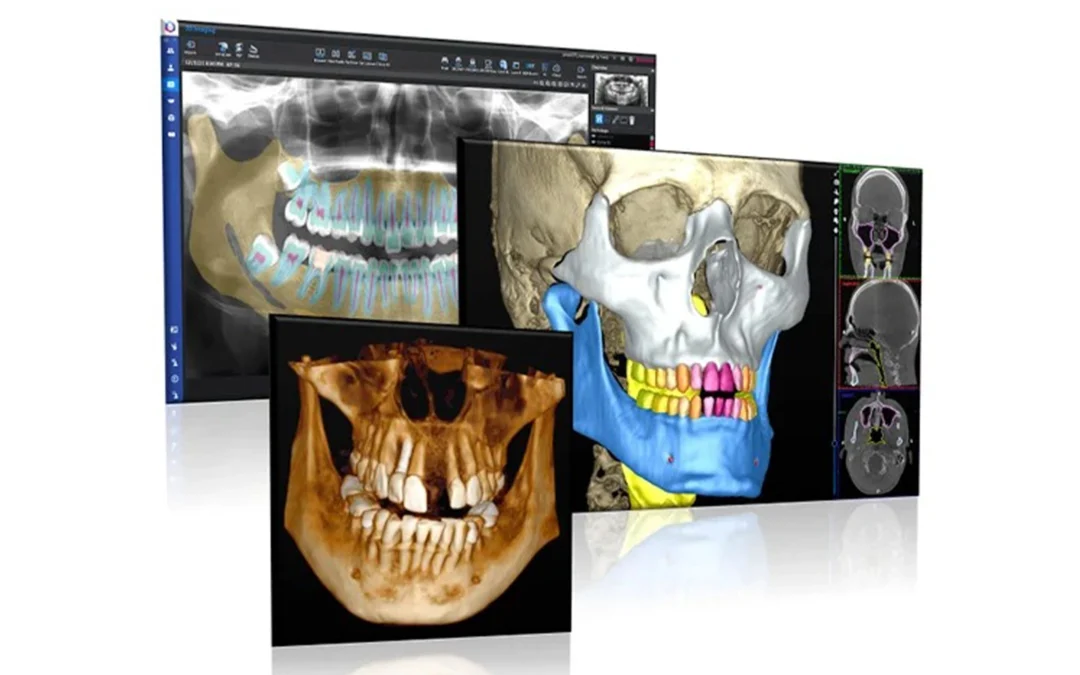

Image Source: AI-Powered CBCT Imaging, Planmeca

Prosthodontics and implant dentistry rely on accurate planning and precise evaluation. AI systems are being developed to assist with the analysis of CBCT scans, identification of implant systems, assessment of bone dimensions, and prediction of restorative outcomes.

While many of these applications remain under active investigation, emerging evidence suggests that AI can support more accurate planning for crowns, bridges, and implants, particularly when integrated into digital workflows.